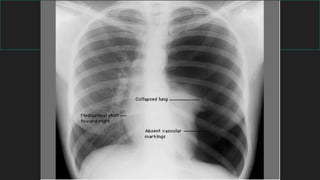

Signos radiológicos principales

Neumotórax

Neumotórax a

tensión